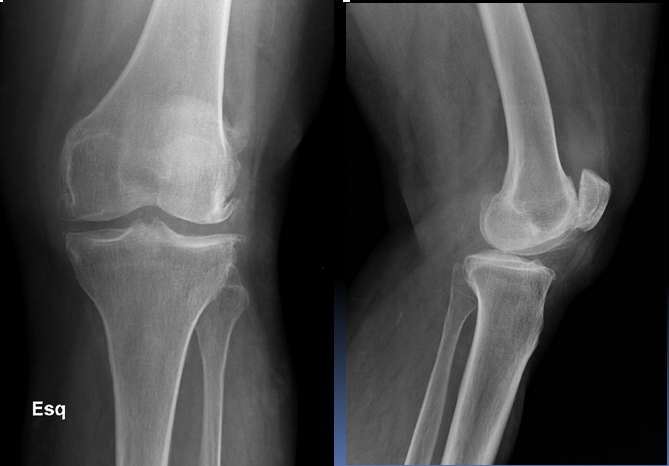

A 30 year old man presented to the ED with left knee pain after a cycling accident.

On examination there was no deformity, but it was painful for him to weight-bear. Movements of his knee were painful, and this limited his movements.

What is a lipohemarthrosis?

Results from an intra-articular fracture with escape of fat and blood from the bone marrow into the joint, and is most frequently seen in the knee.

What normal variant can be seen in this image?